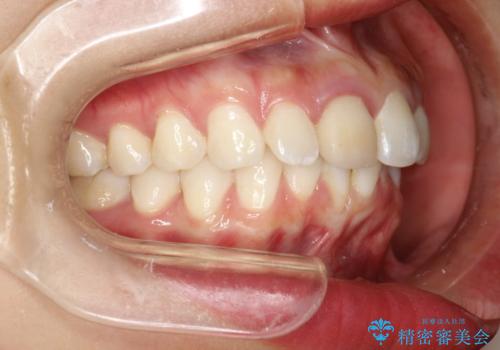

後戻りした歯並びをきれいにしたい

- ワイヤーで矯正した後戻りをマウスピースで治そうとしたが、使えなかったため再度ワイヤー矯正希望で来院されました。

装置はハーフリンガルを選択しています。

右下1が歯肉退縮していたため、アーチを拡げないように歯と歯の間を削って隙間をあけて並べています。